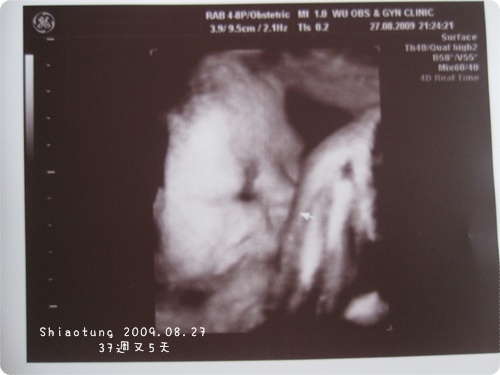

每次都拿到擠臉的照片,

好膩喔!

本來想請醫生給我手或是腳的照片,

但是照超音波太快收場...就算了!

不過手和腳也常常被擠得都彎曲不清楚就是了。

最近的產檢都是拿到這樣的擠臉照片